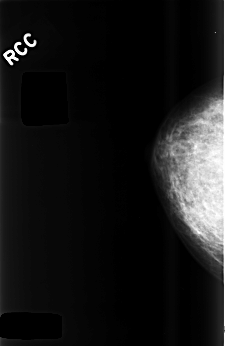

C_0481_1.RIGHT_CC

RIGHT_CC LINES 4488 PIXELS_PER_LINE 2920 BITS_PER_PIXEL 12 RESOLUTION 50 NON_OVERLAY